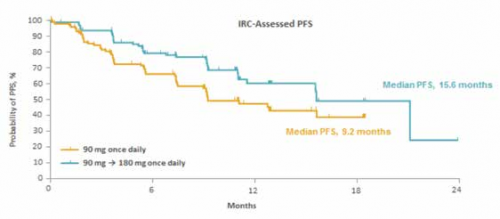

מחקר הרישום של בריגטיניב, ה־alta study, מחקר פאזה 2, רנדומלי, בינלאומי ורב מרכזי, בחן את יעילות ובטיחות התרופה בשני מינונים שונים, בזרוע טיפול אחת החולים קיבלו 90 מ"ג פעם ביום ואילו בזרוע השנייה החולים קיבלו 180 מ"ג פעם ביום אחרי שבוע שבו קיבלו את התרופה במינון של 90 מ"ג ליום, שלימים הפך למשטר הטיפול המומלץ’[7][16],

במחקר ה־ alta הציגה בריגטיניב יעילות משמעותית בשילוב עם פרופיל תופעות לוואי טוב. במחקר נכללו 222 חולים שחולקו לשתי זרועות הטיפול, כולם אחרי טיפול בקריזוטיניב, כ־70 אחוזים מהם עם גרורות במח וכ־70 אחוזים טופלו קודם לכן גם בכימותרפיה[7].

בזמן פרסום האנליזה, כפי שפורסמה ב־ Journal of clinical oncology בחודש מאי האחרון, משך המעקב אחרי החולים בזרוע הטיפול במינון המומלץ* עמד על 8.3 חודשים. הזמן החציוני של ההישרדות הכוללת (mOS) טרם הושג ולאחר שנה אחת של מעקב 80 אחוזים מהחולים עדיין היו בחיים. חציון ההישרדות ללא התקדמות מחלה (mPFS) עמד על 12.9 חודשים, לפי הערכת החוקר, ועל כ־15.6 חודשים על פי הערכת הוועדה החיצונית. שיעור התגובה (orr) עמד על 54 אחוזים, עם 4 אחוזים שחוו תגובה מלאה ((CR)[7]. לפיכך, מבין כלל תרופות הקו השני, בריגטיניב מציגה את התוצאות הטובות ביותר עם mPFS כפול אף מזה של קריזוטיניב בקו הראשון. (תרשים 2)